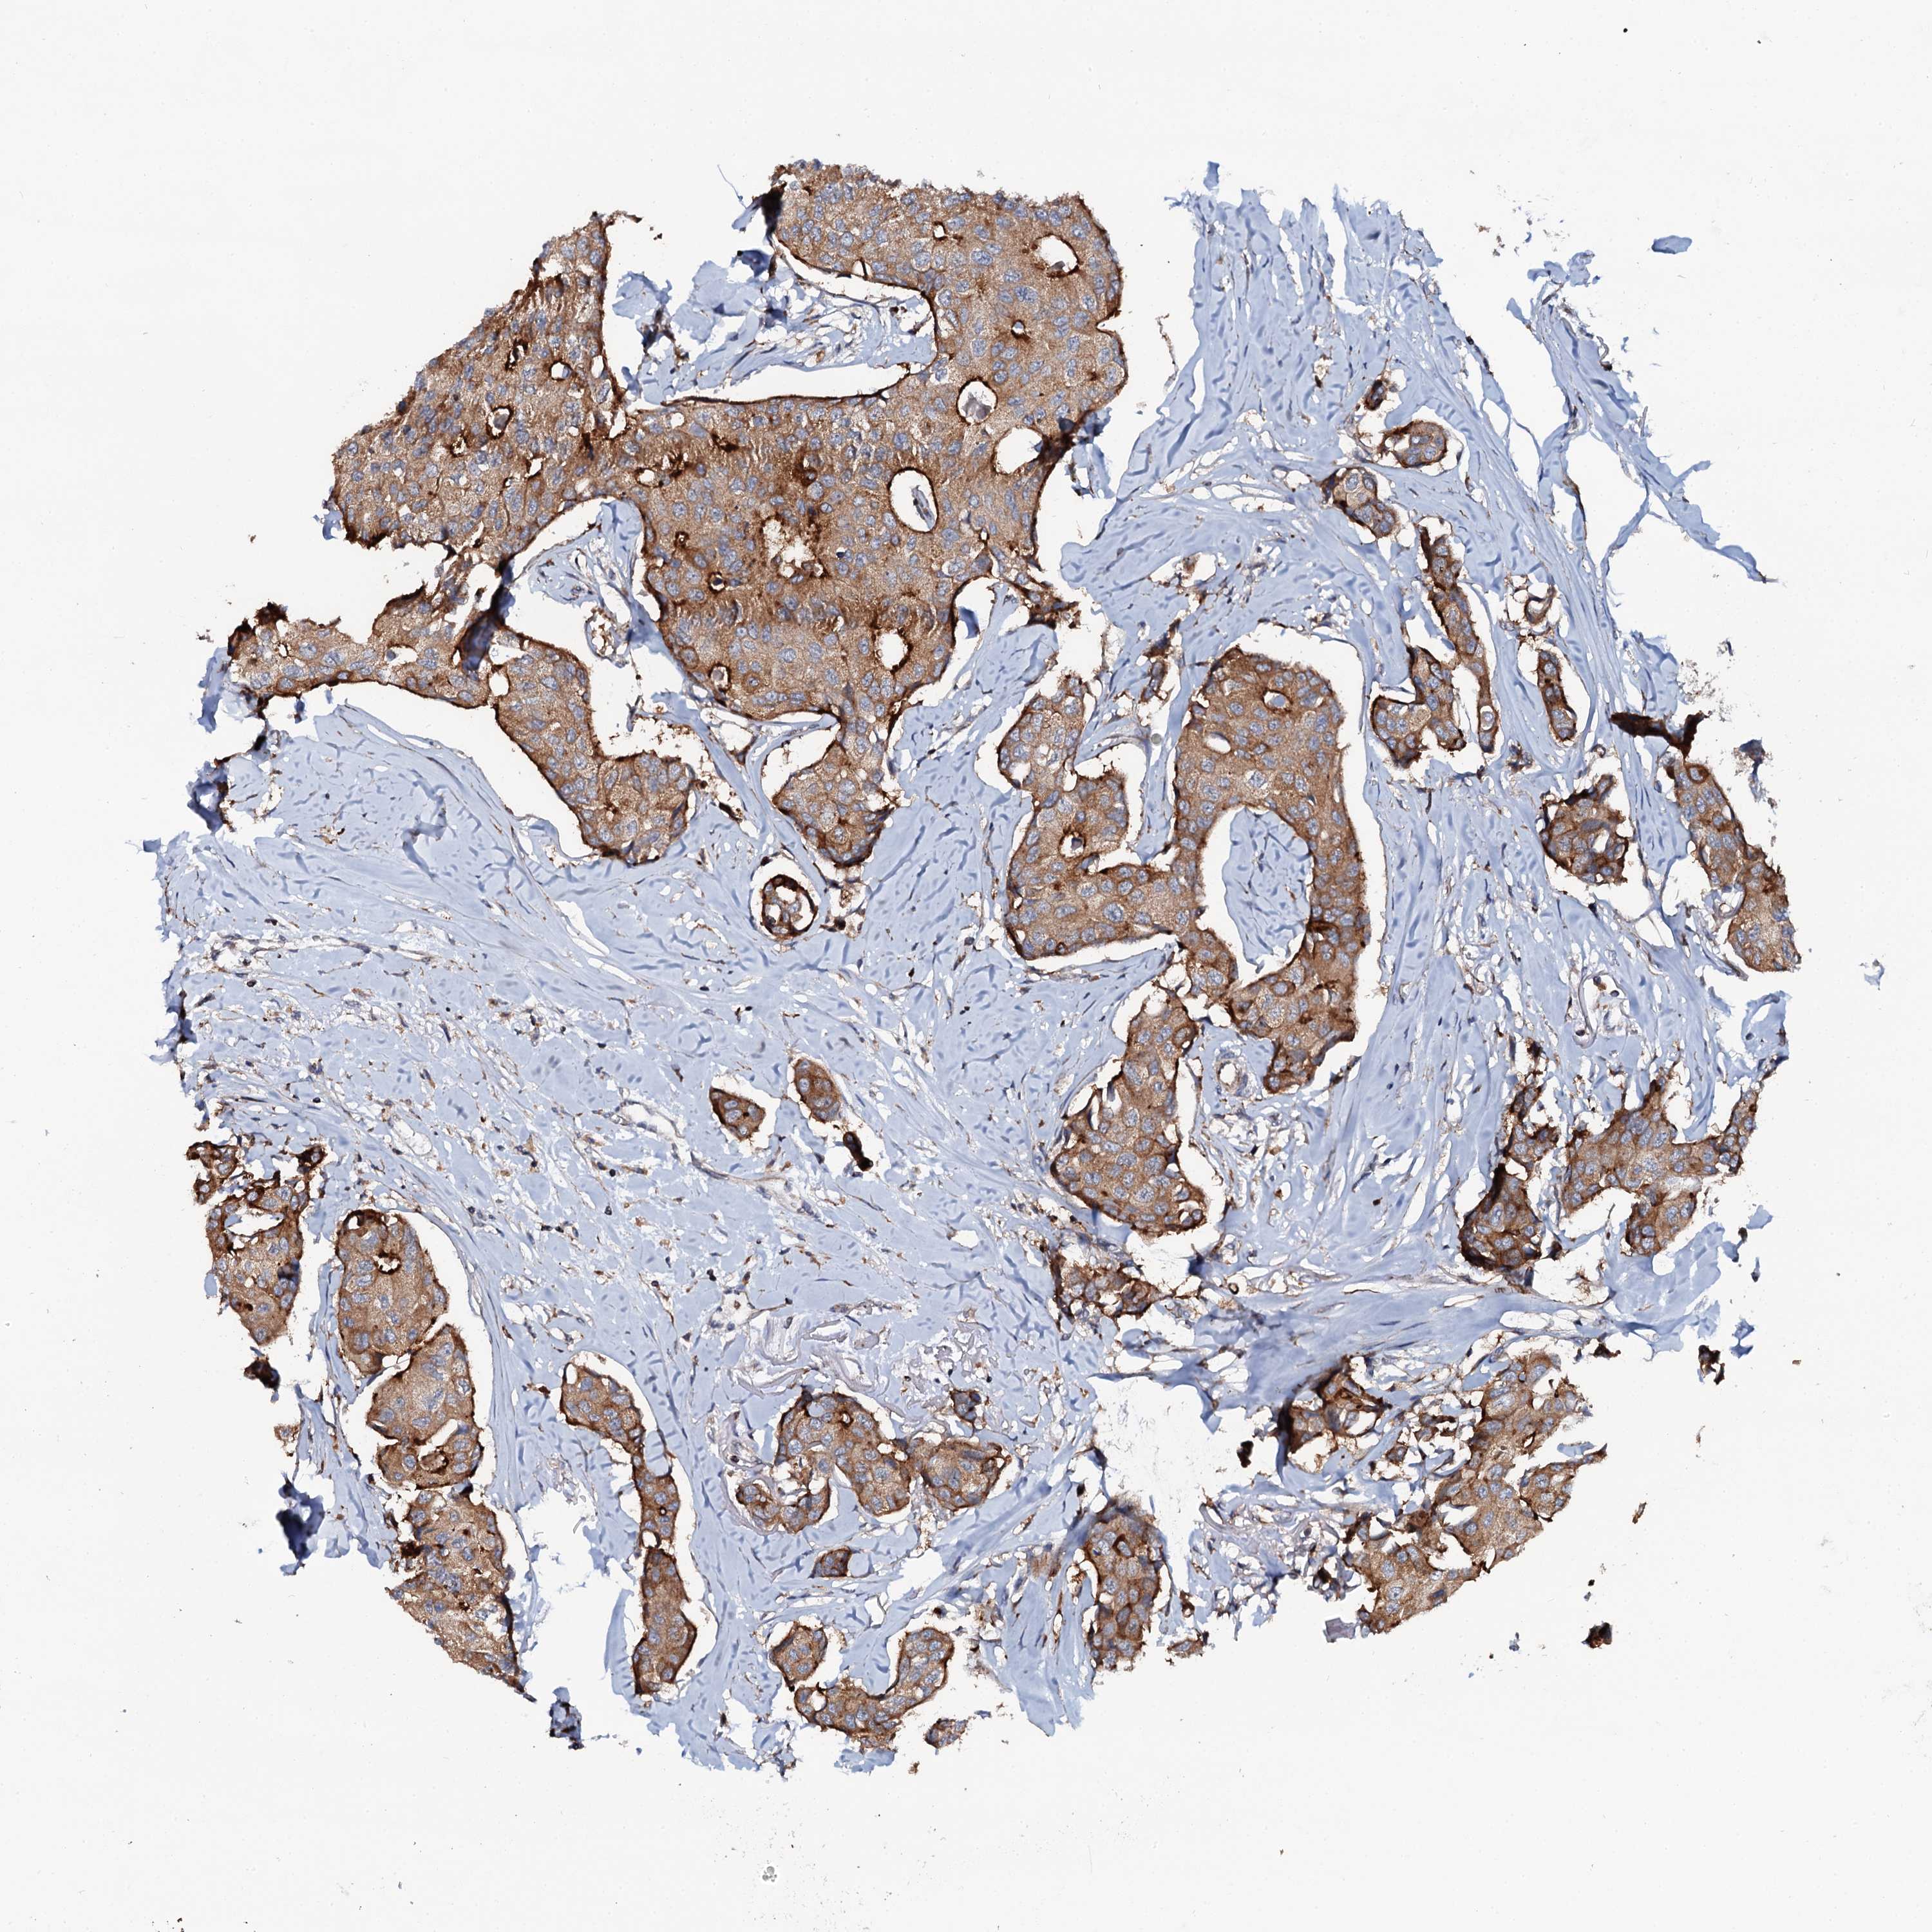

CANCER BREAST CANCER Show tissue menu

BRCA TCGA BRCA VALIDATION PROTEIN EXPRESSION

Breast cancer

Human cancer